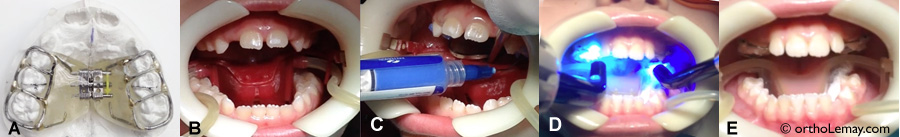

Comment est posé un appareil d’expansion?

La pose d’un appareil d’expansion fixe collé sur les dents ne prend que quelques minutes. Pour voir comment est posé cet appareil, suivez le lien ci-dessous.

vis app expansion

La vis d’un appareil d’expansion peut être ouverte de plus de 1 cm afin d’élargir le palais.